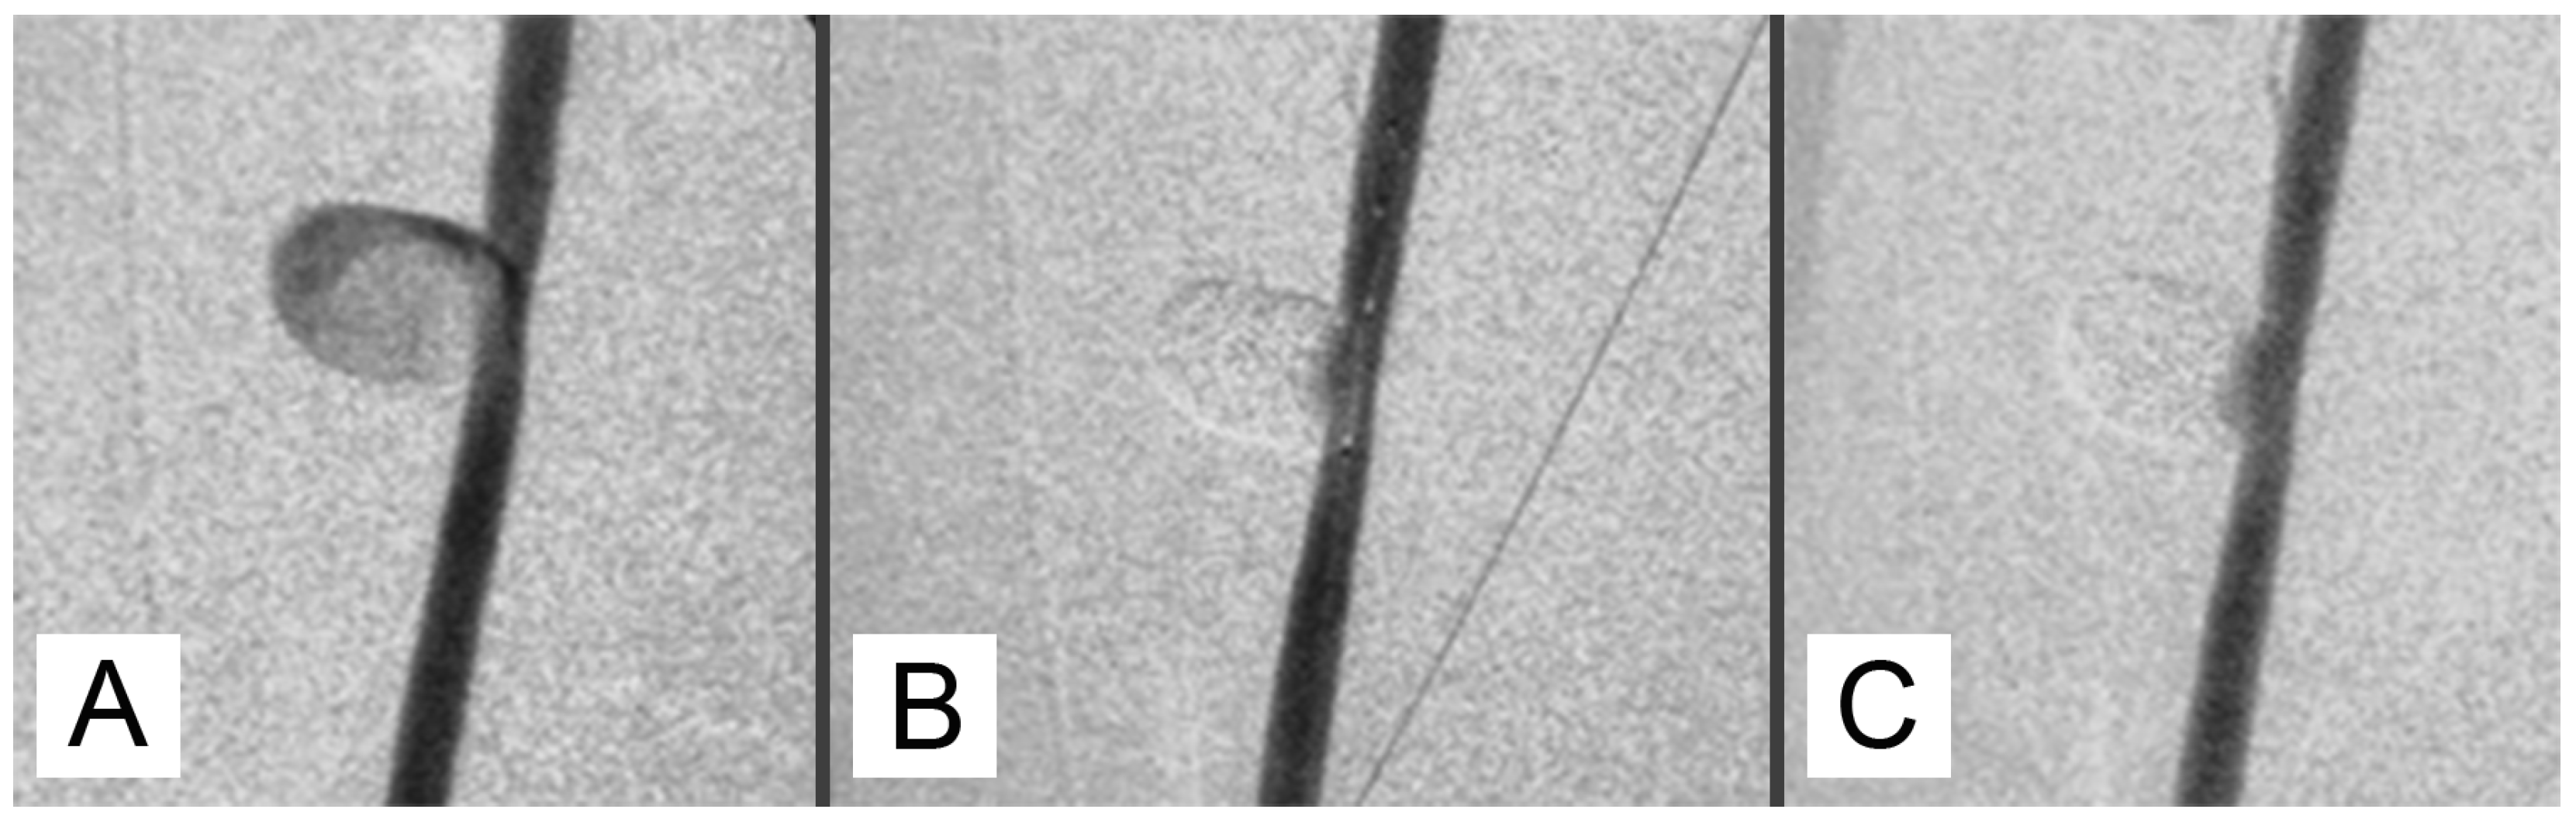

The subjects sampled at 7, 30, and 90 days post-surgery did not exhibit symptoms related to a painful state or signs of side effects after aneurysm embolization. During the surgery for removing the experimentally induced defects, no alterations due to an ongoing inflammatory process were evidenced (Figure 2C). The mean long × short diameters of the created aneurysm ranged from 5 to 30 mm (mean diameter 12.4 mm ± 6.2 mm). The mean neck width ranged from 3 to 10 mm. The dome-to-neck ratio (long diameter/neck width) ranged from 1 to 3. A complete occlusion was observed starting from time 0 (Figure 3A) and remained evident at 7 (Figure 3B), 30 (Figure 3C), and 90 (Figure 3D) days post-surgery. The aneurysm occlusion was due to a mixture of the embolic agent and thrombotic materials. The distribution of the embolic material inside the embolic cast was homogeneous, and the embolizing material adhered to the aneurysm wall. There was no evidence of recanalization of the embolic cast in samples examined, particularly after 7, 30, and 90 days post-surgery.

Figure 3. Aneurysms embolized using the modified mixture. (A) After the embolization, complete occlusion due to the embolizing mixture resulting as a refractile material was evident (H-E, bar = 0.5 cm). (B) One week post embolization, the aneurysm lumen was filled by the embolizing mixture mixed with fibrin, and small hemorrhagic areas were evident close to the wall of the structure (H-E, bar = 1 cm). (C) Thirty days after surgery, the aneurysm was completely occluded by the modified mixture (H-E, bar = 0.5 cm). (D) Ninety days after embolization, the aneurysm lumen was still occluded, and recanalization phenomena were not evident (H-E, bar = 0.5 cm).